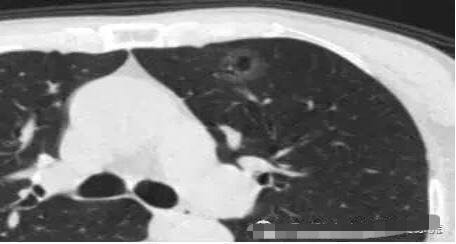

病例1 .

2014年 首次发现右肺上叶GGO,病灶直径8.3毫米, 2016年复查发现右肺上叶GGO,病灶直径12.4毫米。2年大约生长4毫米,平均1年生长2毫米。2016年手术病理结果:浸润性腺癌。

2014年 病灶8.3毫米